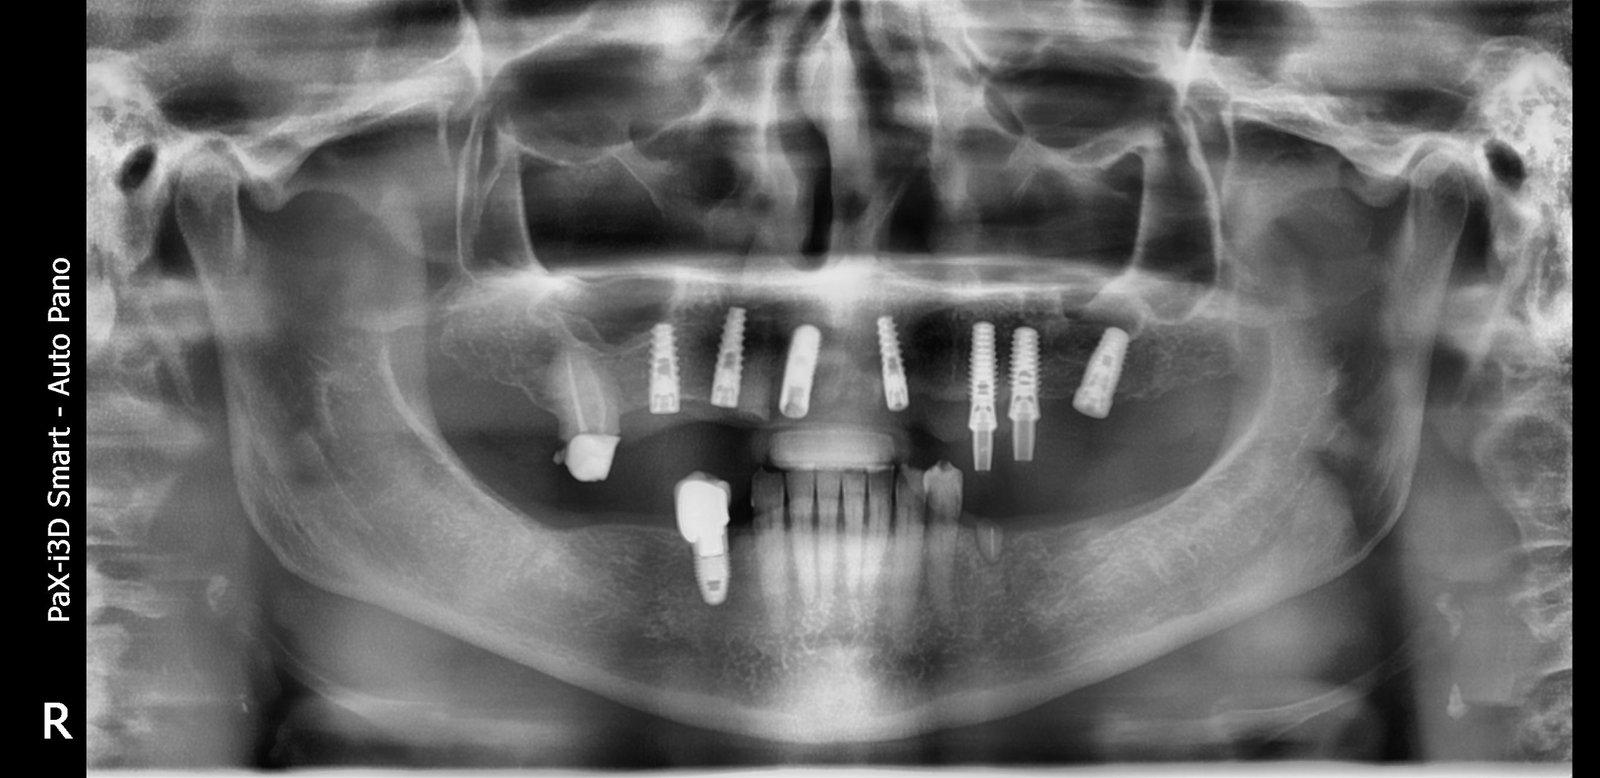

Buenos noches... Subo caso recibido.

Necesito identificar implantes superiores para cambiar protesis

Buenos días!! Este paciente nos visita por fractura de tornillo!

Tiene las bolas gastadas y las tengo que cambiar. Gracias y saludos